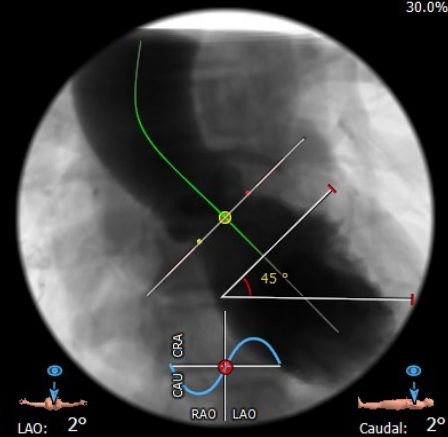

全麻下建立双侧股动脉入路,以右股动脉为主;导丝跨瓣后置换猪尾导管,确定共平面。

图片